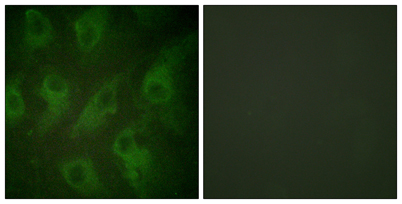

Product name: KIR6.2 rabbit pAb

Dilutions: Western Blot: 1/500 - 1/2000. Immunohistochemistry: 1/100 - 1/300. Immunofluorescence: 1/200 - 1/1000. ELISA: 1/10000. Not yet tested in other applications.

Cellular localization: Membrane; Multi-pass membrane protein.